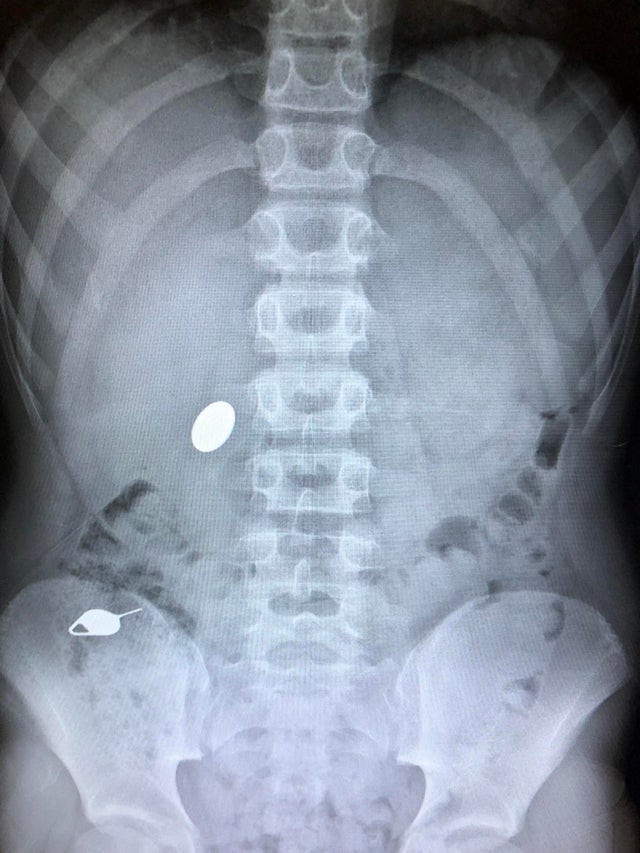

1. «Сын проглотил монетку, пока показывал брату, как он за день до этого проглотил ключ»